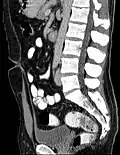

Midsagittal CT scan of a man's abdomen showing the urachus